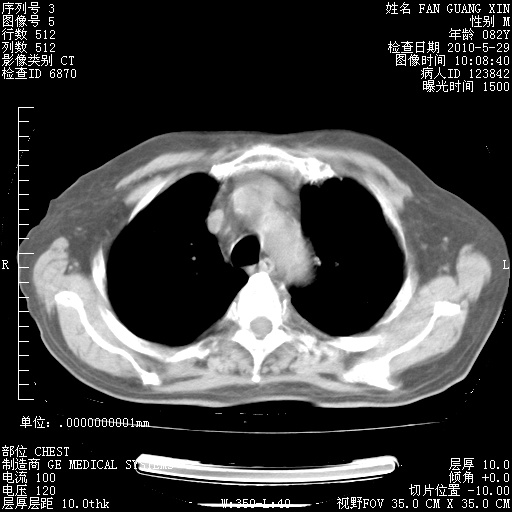

再治疗10天后的肺部CT

阅读此次胸部CT,肺间质渗出性改变较入院时有吸收。目前从体温、白细胞、中性分叶明显增高,肯定存在细菌感染(发生医院感染哦,若无消化道及泌尿系统等感染的依据,肺部感染可能大)。若你院头孢哌酮舒巴坦钠耐药率较高,同意你的方案,若48小时体温仍高,可考虑使用碳青霉稀类抗菌药物,同时可予超声雾化、注意滴数时加大液体量。白蛋白33.30g/L较低哦,需加强营养等支持治疗。